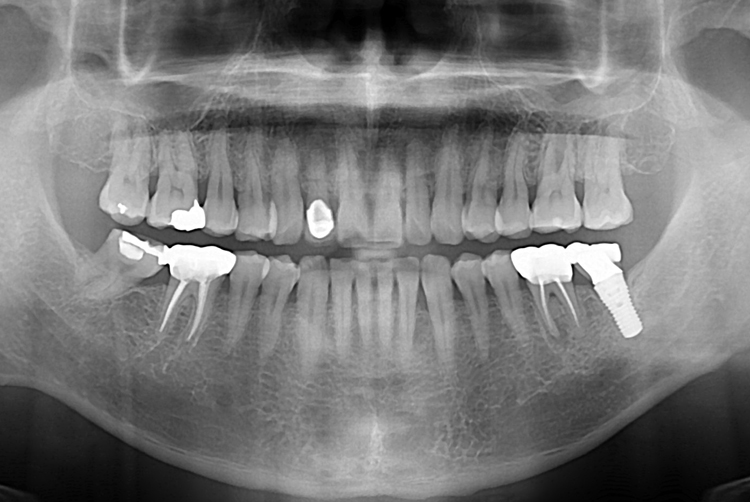

[임플란트] 어금니 임플란트

치료후 : 2018-08-22

세종치과는 많은 환자와 다양한 케이스를 바탕으로

항상 편안한 임플란트 수술을 제공하고자 노력하고,

오래동안 튼튼히 쓸 수 있는 임플란트 수술을 가장 큰 목표로 삼고 있습니다.